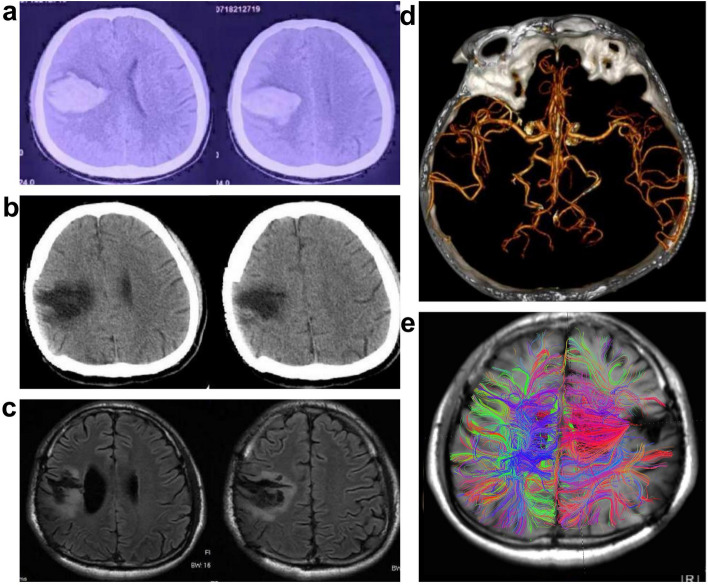

Case presentation: This report presents a case of a patient who developed left upper limb hemiplegia and recurrent seizures after a hemorrhagic stroke. The patient showed a poor response to standard anti-epileptic treatment and was diagnosed with stroke-related epilepsy. To manage the recurrent seizures, VNS was performed. After the device was activated, the patient reported a significant reduction in abnormal muscle tone and increased mobility impairment in the affected upper limb. Parameters were adjusted, and intermittent stroke electrical stimulation was combined with upper limb rehabilitation exercises. After three months of active treatment, the patient's seizures were well controlled, and there was significant improvement in upper limb function.